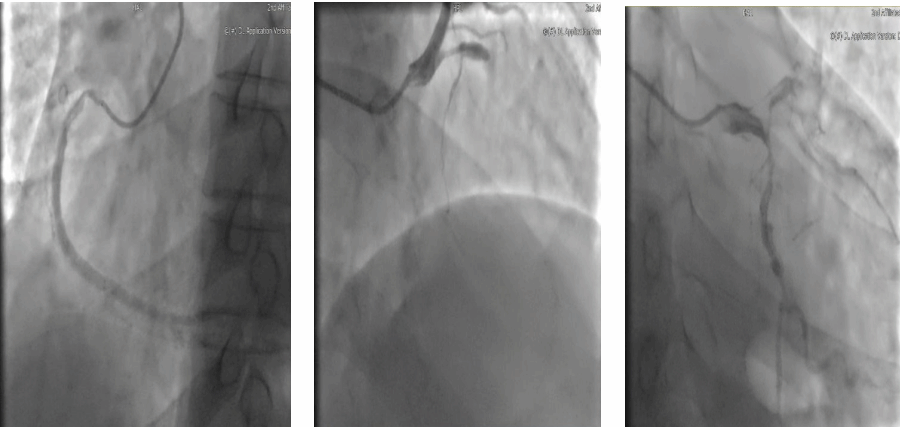

“才54岁,胸痛两年一直忍,检查结果出来全家都慌了!”近日,来自陕西的张先生因严重冠心病就诊于我院,冠脉造影显示心脏三支主要血管严重堵塞,随时可能引发心梗。传统搭桥手术通常采用“静脉+动脉”组合,但静脉桥容易老化。考虑到张先生年龄较轻,为提高远期疗效,心血管外科高峰主任团队制定“全动脉化搭桥”方案——用更坚韧的动脉血管作为“新生命线”,为患者争取更优质的生活质量,最大可能地提高远期生存率。

手术当日,在麻醉科、手术室多团队配合下,高峰主任凭借丰富手术经验,选取左胸壁的乳内动脉搭建前降支桥,用双侧前臂桡动脉完成另外两处搭桥(乳内动脉-前降支,桡动脉-第一钝缘支-第二钝缘支,桡动脉-后降支)。这种“三桥联建”方案既保证了充足的血流,又最大限度保护了血管功能。此外,术中还同步完成两项精细手术操作,为严重钙化的血管实施“内膜剥脱术”清除斑块,对异常心肌束进行“肌桥松解术”解除压迫。手术历时4小时,4根动脉桥血管完美吻合,血流监测仪显示桥血管流量及阻力指标良好。术后5小时患者清醒,当晚脱离呼吸机恢复自主呼吸,术后第3天即转回普通病房。查房时患者感慨:“原来胸口像压着大石头,现在呼吸都轻快了!”术后7天,患者顺利出院。